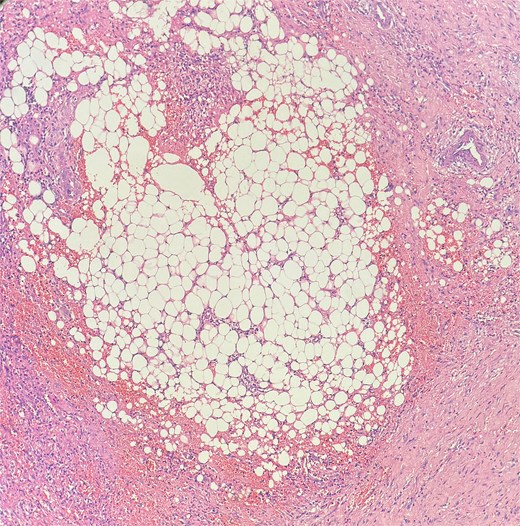

The patient underwent examination under anesthesia and exicision and biopsy (Fig. 4) of the extra-luminal growth via perianal route under spinal anesthesia. A curvilinear incision was made in the right perianal region from 7 o’ clock to 11 o’clock position, 1 cm away from the anal verge to access the tissue, which was then excised in toto and sent for histopathological examination. The cavity was left open to heal by secondary intention. Histopathological examination (Figs 5–7) which was a definitive diagnosis revealed features suggestive of panniculitis. This was the key diagnostic test, confirming perianal panniculitis rather than a fistula or malignancy.

Picture depicting evidence of fat necrosis in the excised perianal tissue.

Sections show a dense inflammatory infiltrate within the subcutaneous adipose tissue, consistent with panniculitis. The infiltrate is composed of neutrophils, lymphocytes, plasma cells, and histiocytes.

Histopathological examination showed ghost-like adipocytes and foamy histiocytes.